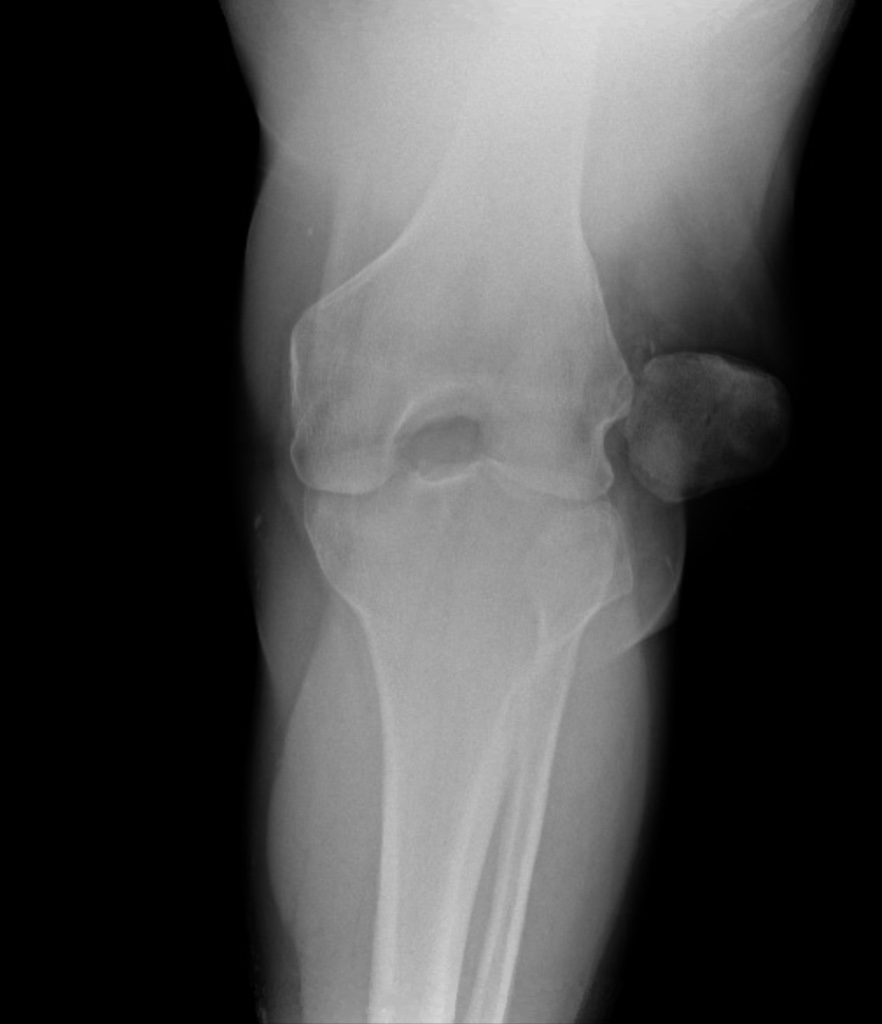

A 55 yo male presents with left knee pain. He reports he slipped in mud and fell onto left knee. He has severe pain and is unable to bear weight. There is an obvious deformity and his knee is held in flexion. The left lower extremity has intact sensation and 2+ dorsalis pedis pulse with brisk capillary refill. An xray is shown. What's the diagnosis? Scroll down for answer.

Answer: Acute patellar dislocation